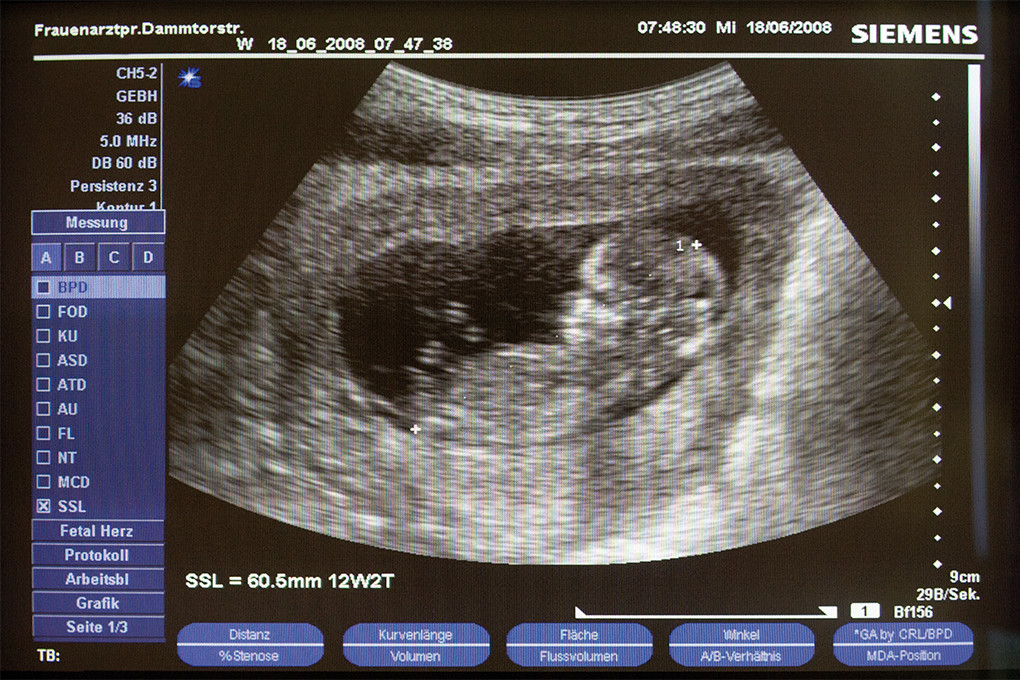

Schwangerschaft

Die sorgfältige und umfassende Betreuung von Schwangeren ist uns wichtig. Nach der Feststellung der Schwangerschaft folgt die individuelle Begleitung mit Vorsorgeuntersuchungen und Ultraschall in 3D-Darstellung. Auch über die regelmäßigen Besuche hinaus sind wir immer an Ihrer Seite.

Sollte bei Ihnen eine  Risiko-Schwangerschaft vorliegen, sind Sie hier bei uns in den sichersten Händen.